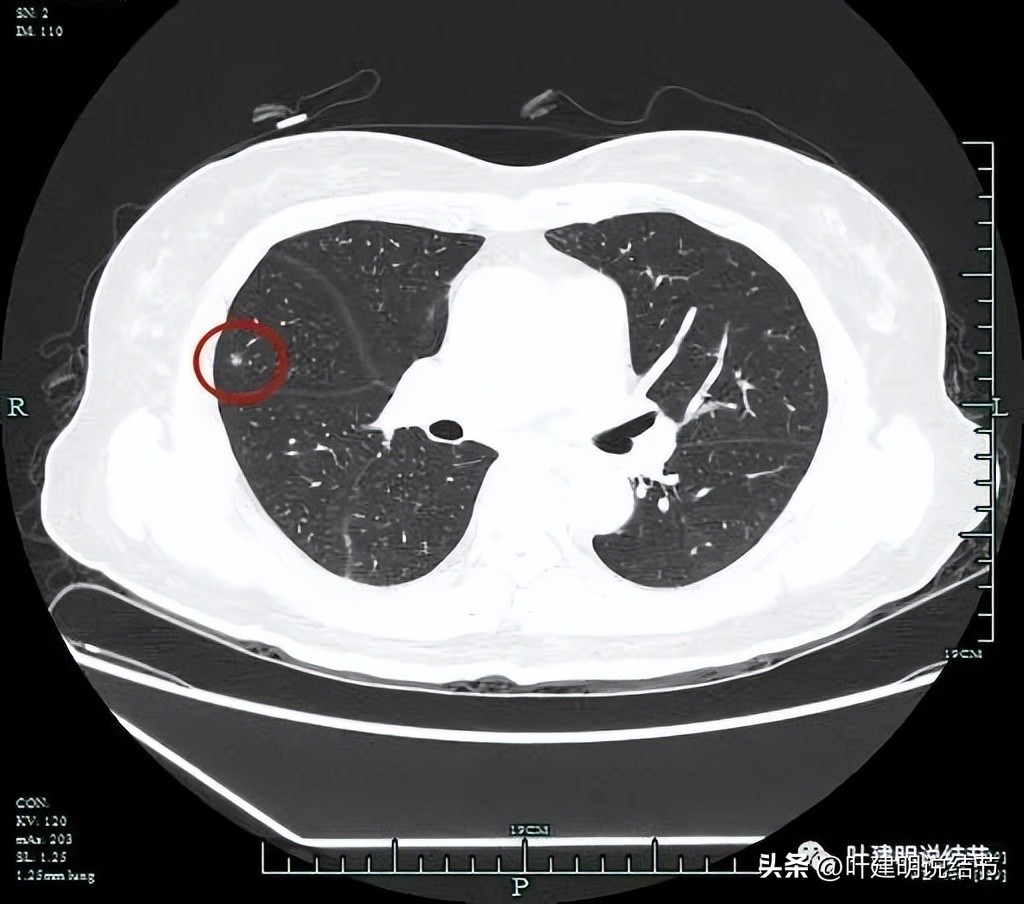

平扫上病灶位置右中叶,较小,但密度并不低,是混合磨玻璃的样子。

甚至有微血管进入的表现。